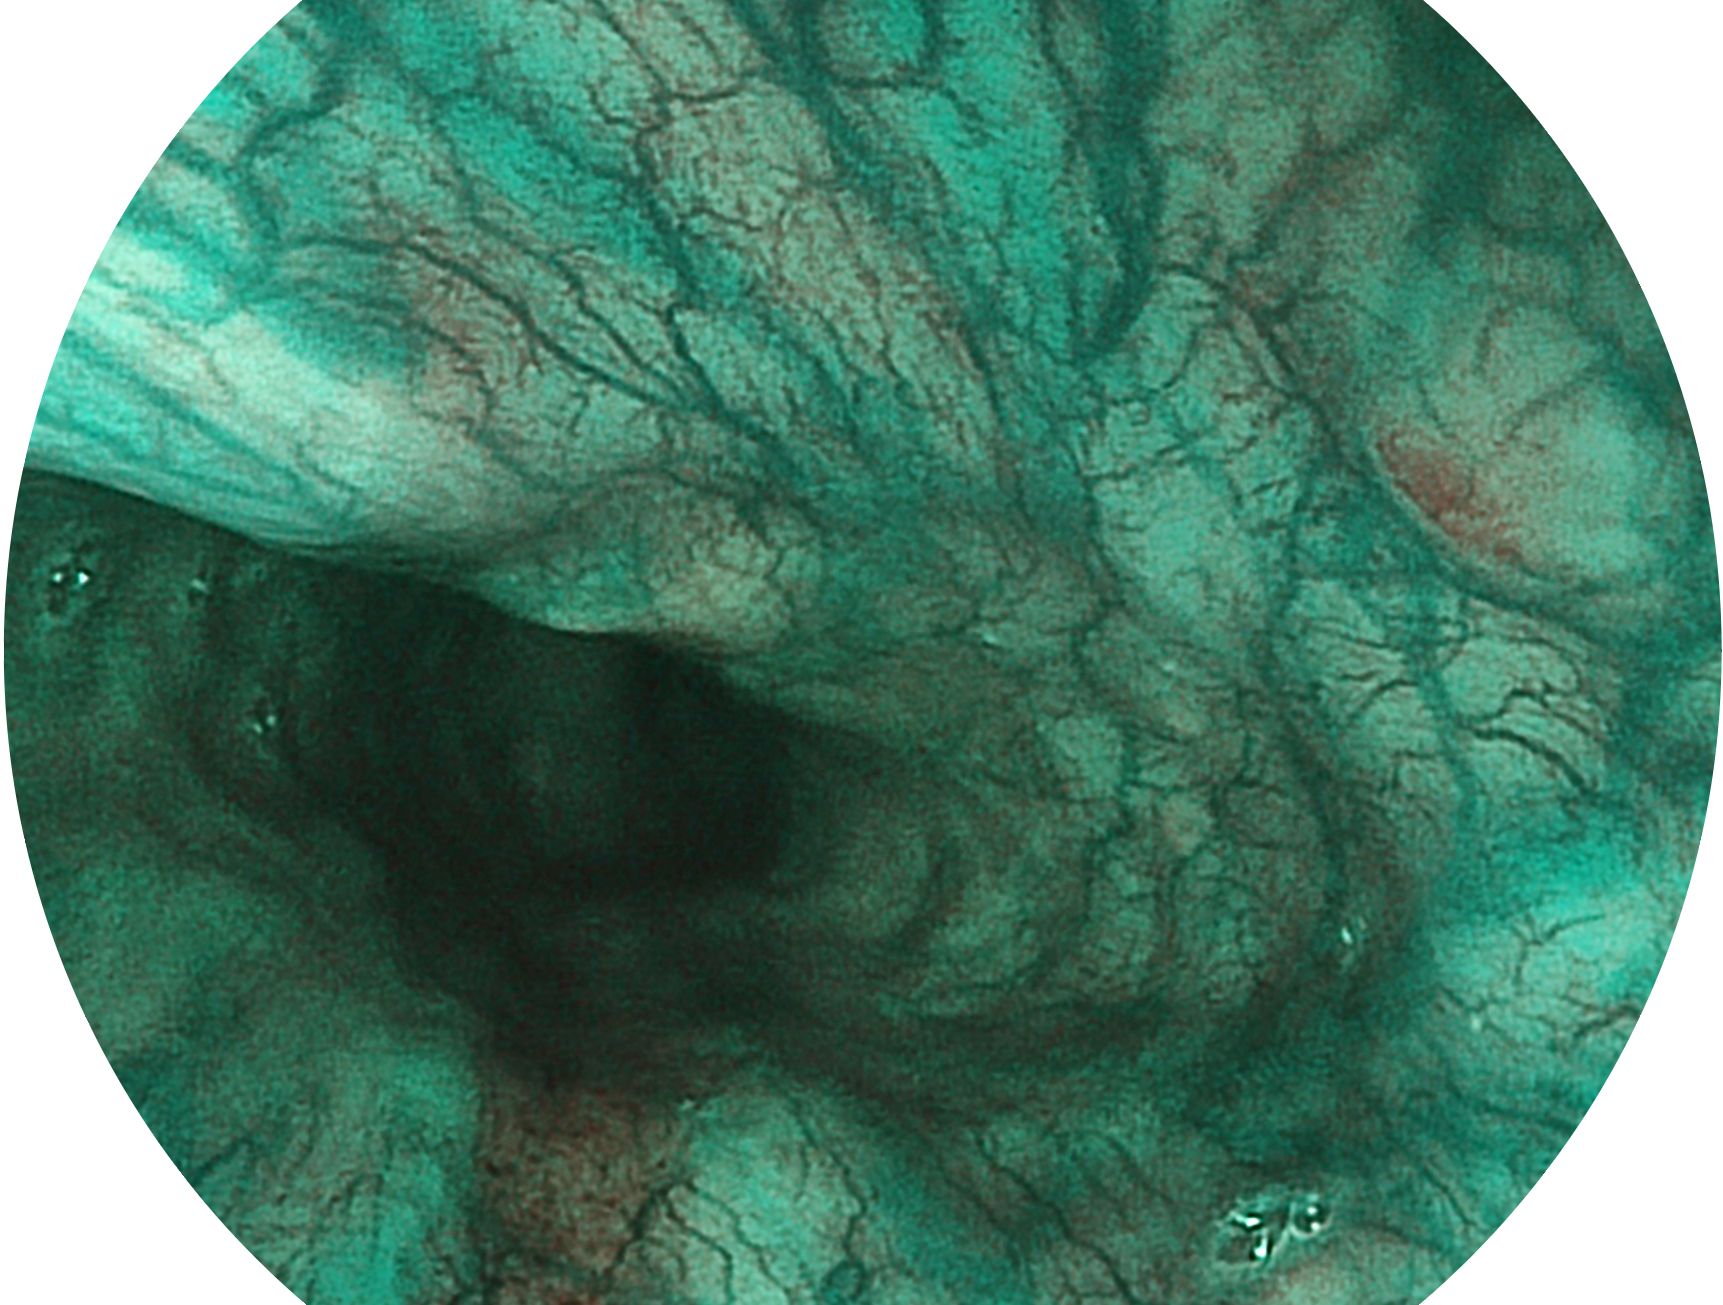

米兰官方网站新开发的内镜染色技术,主要是基于多波长LED 光源的开发,VLS-55Q 四波长LED 光源是由四个不同颜色的LED光按照相应照明模式所规定的特定发光比例进行合束后形成,合束后形成的照明光的光谱由红光、绿光、蓝光及蓝紫光这四个不同的波段范围构成。具有更高光谱自由度,通过光谱比例的控制,实现了聚谱成像技术,英文全称为“Spectral Focused Imaging, SFI”,缩写为“SFI”和光电复合染色成像技术,英文全称为“Versatile Intelligent Staining Technology, VIST”,缩写为“VIST”。